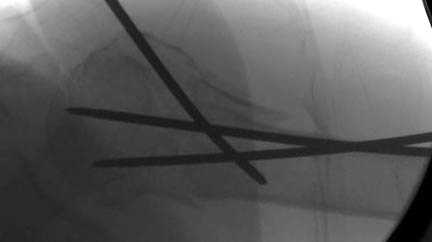

Наш недавний случай перкутанной фиксации "методом

Сиэтла" спицами 2.8 мм с резьбой на конце.

Головка плечав небольшом варусе или это проекционное?

-Головка плеча в небольшом варусе или это

проекционное?

Да, там имеем небольшой варус, надеемся, что в будущем проблемы не будет.

Из-за большого обьема конечности доступ к бугорку был затруднен, предварительно зафиксированный шуруп не удержал бугорок, поэтому фиксацию провели толстыми нитками. Состоятельность фиксации бугорка обычно проверяем во время операции, под рентген контролем проводится движения конечности, особенно приведение.